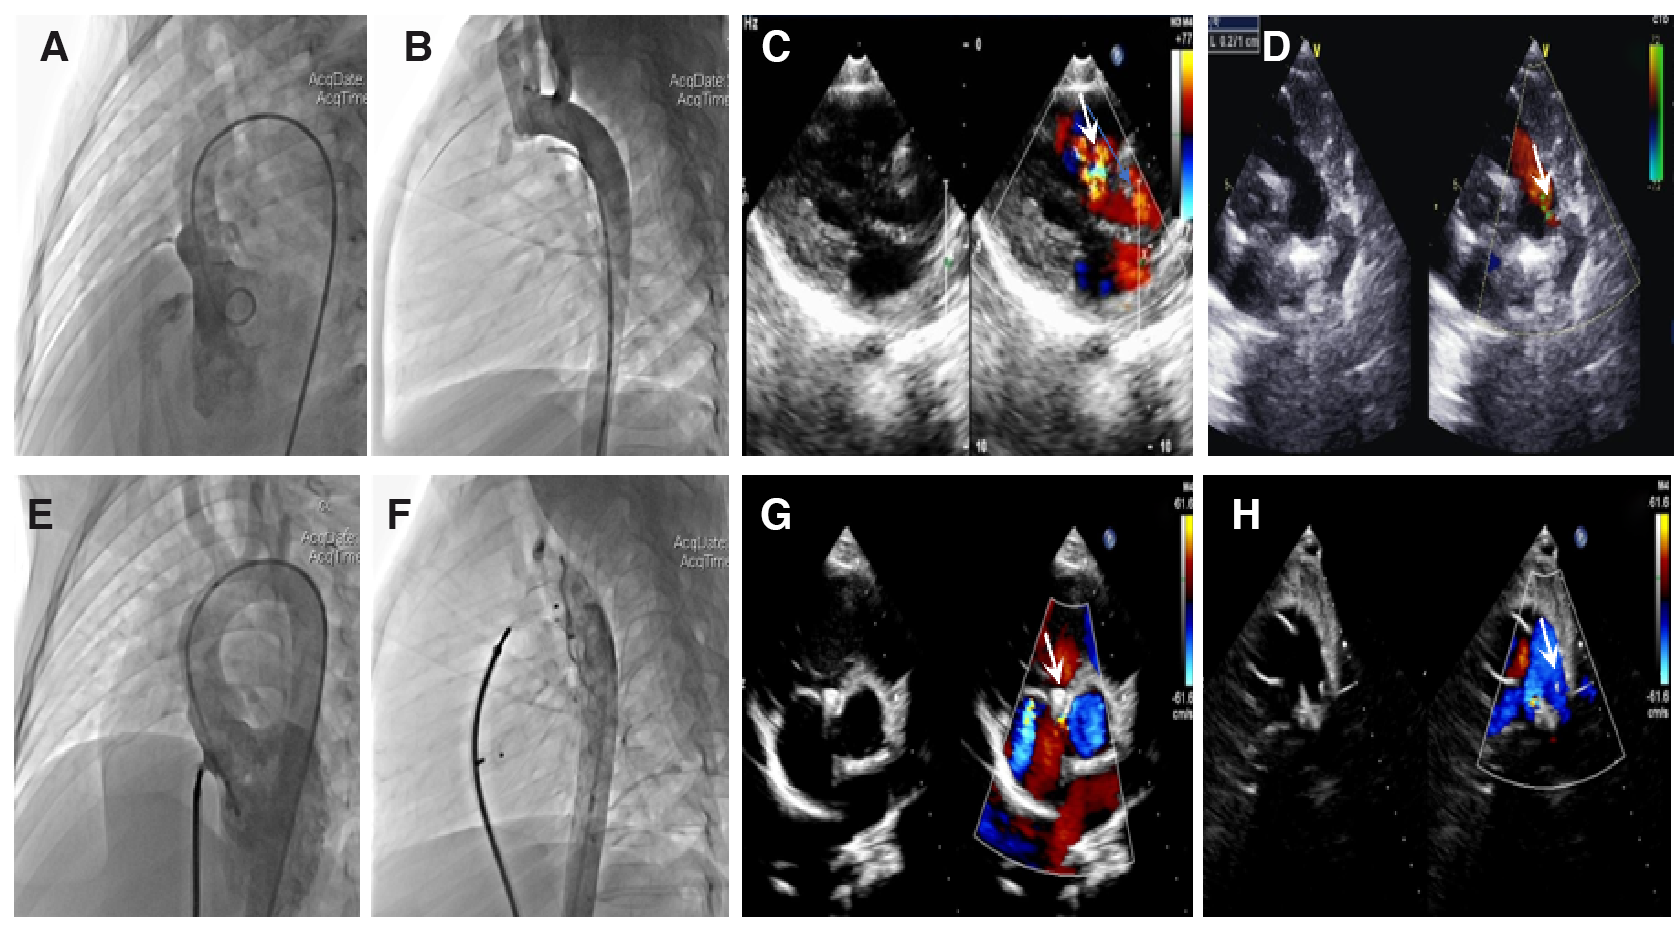

During the procedure, all patients underwent successful simultaneous interventional therapy. The positions of the occluders were well fixed, and no severe residual shunt or valve regurgitation was detected on TTE (Figure 1). TTE revealed a significant change in PG, which imminently decreased from 47.3 ± 21.9 mmHg to 15.2 ± 12.2 mmHg after PBPV (Figure 2). No complete atrioventricular block (cAVB) was found by ECG, and the average time of intervention was 66.7 ± 28.9 min.

Figure 1

Angiocardiography and echocardiography images in a patient with ventricular septal defect (VSD) combined with patent ductus arteriosus (PDA). Preoperation: (A) Long-axis view of the left ventriculography showing a significant left-to-right shunt through the VSD. (B) Lateral view of the aortic angiography showing an evident shunt from the aorta to the pulmonary artery through the PDA. (C) Parasternal left ventricular long-axis view showing a left-to-right shunt passing through the VSD. (D) Parasternal short-axis view at the base of the main pulmonary artery (MPA) and its branches showing a shunt from the aorta to the pulmonary artery through the PDA. Postoperation: (E) No evident shunt is detected after VSD occlusion by left ventriculography. (F) No aortopulmonary shunt is detected. (G,H) Parasternal short-axis view showing that the VSD and PDA occluders are properly placed; no evident shunt is detected. The white arrow points to the defect and occluder.